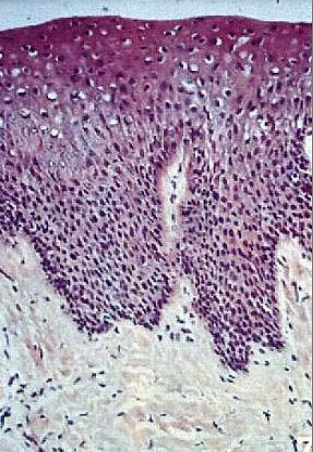

what type of epithelium is this

masticatory mucosa- keratinized epithelium